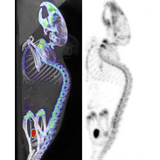

The β-CUBE is our high-performance preclinical PET imager.

Sub-millimeter image resolution is achieved through the combination of monolithic scintillators, the latest photon counting technology and GPU-based event positioning and iterative image reconstruction. The 5-ring configuration ensures best-in-class sensitivity over a field-of-view adequate for whole-body mouse and rat imaging at high count rate. In-house hardware allows for dynamic and gated studies. Intuitive and wireless acquisition software combined with our multimodal small animal bed allow for easy and modular multimodal imaging along with the γ-CUBE (SPECT) and X-CUBE (CT).